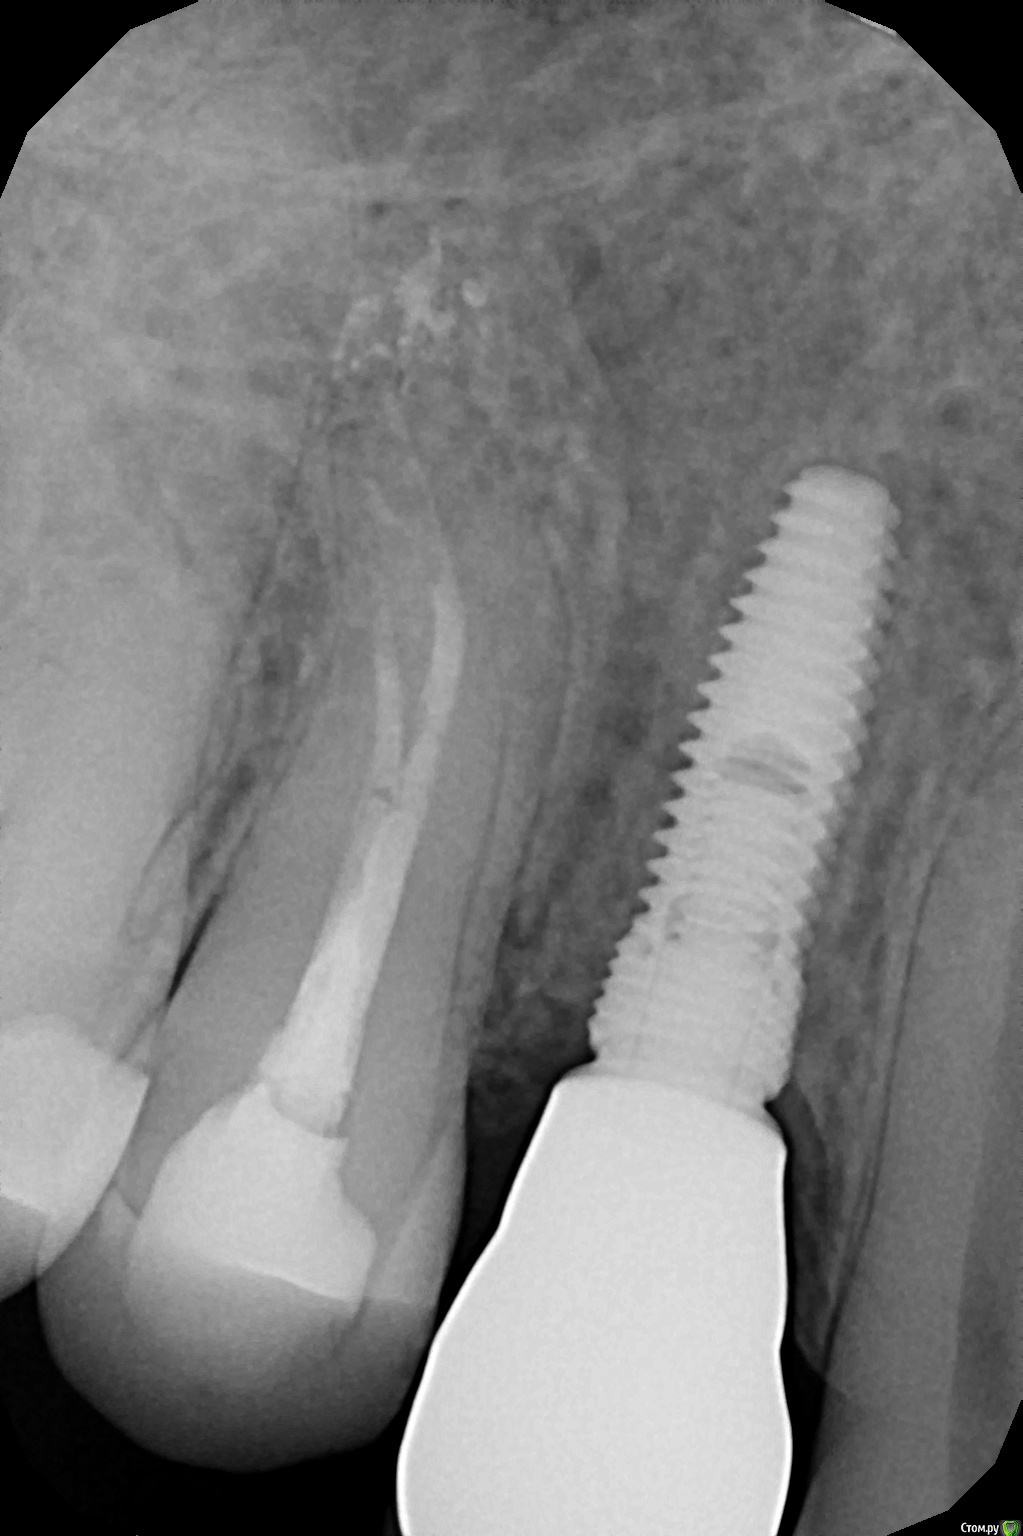

dok1 Опубликовано 13 января, 2018 Поделиться Опубликовано 13 января, 2018 Выложите снимок импланта. Может узнаем. Ссылка на комментарий

Zedan Опубликовано 17 января, 2018 Автор Поделиться Опубликовано 17 января, 2018 в любой клинике с визиографом Вот он Ссылка на комментарий